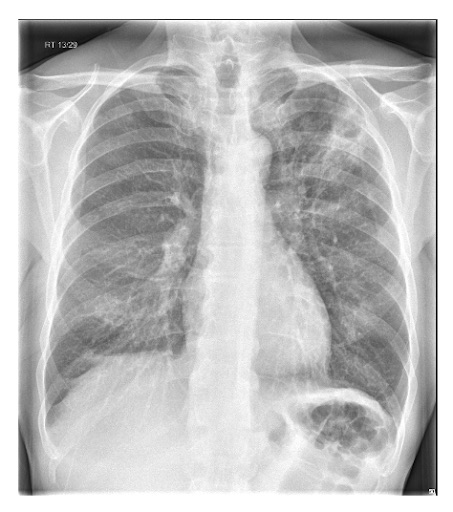

O diagnóstico definitivo de PAC requer evidências de consolidação na radiografia torácica.[1][63][65][75] Faça uma radiografia torácica em todos os pacientes que se apresentarem no hospital o mais rápido possível e dentro de 4 horas após a admissão.[Figure caption and citation for the preceding image starts]: Radiografia de tórax posteroanterior mostrando consolidação do lobo superior direito em um paciente com pneumonia adquirida na comunidadeDurrington HJ, et al. Recent changes in the management of community acquired pneumonia in adults. BMJ 2008;336:1429. [Citation ends].